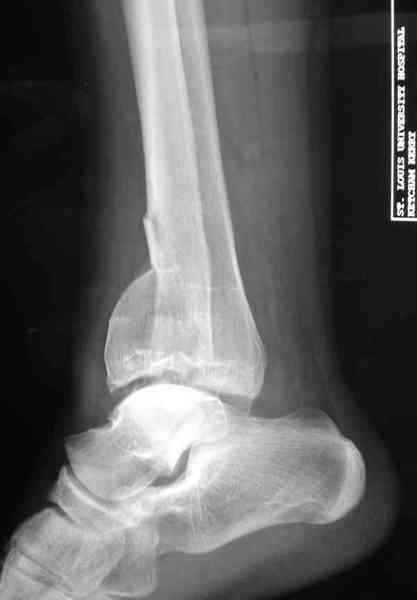

Снова приветствую вас, коллеги. К моменту вступления в обсуждение аксакалов, операция была, увы, выполнена(31.10.07.) Начали с доступа к наружной лодыжке, произвели ее фиксацию спицами, развернули кусок заднего края, наложили дистрактор, затем произвели дистракцию, фиксацию спицами дистального эпиметафиза б/бк,Рентгено-контроль. синтез наружной лодыжки 1/3пластиной. из двух коротких разрезов сформирован канал под медиальную тибиальную пластину LCP. Края ран ушиты без натяжения. Прочувствовать жесткость фиксации винтами с угловой стабильностью не удалось, поэтому дистрактор оставлен на энное время.

На представленных R-снимках не окончательный вид после остеосинтеза. Дистальная опора давила на стопу, пришлось ее сместить проксимально, в рез-те чего, она закрыла щель сустава, последние снимки не информативны.

Нижний винт, похоже, длинноват.

Дистальные винты как-то чуть не все идут не в дистальные отломки, а в зону перелома. И действительно, присоединяюсь к вопросу Якова - в диафизе так и оставили 1 винт?

Честно признаться тяжело на душе после такой операции,-было всё хорошо после первоначальной дистракции, хорошая редукция отломков, после остеосинтеза пластинами появилась подвывых стопы кнаружу, от пластини LCP никакой толку-дистальные винты в зоне излома и дистальный отломок не охвачен, проксимально всего один винт, дистальные винты из м/б кости проходят сквоз сустава и упирается в таранку, стопа в эквинусном положении.Если даже всё обойдется, этот сустав нормально не будет работат.